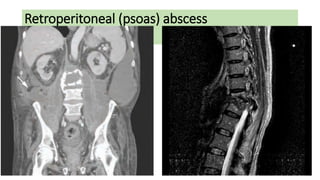

Retroperitoneal (psoas) abscess

Clinical presentation

• Back pain, lassitude and fever.

• A swelling may point to the groin as it tracks along iliopsoas.

• Pain may be elicited by passive extension of the hip

• or a fixed flexion of the hip evident on inspection.

Retroperitoneal (psoas) abscess Clinicalpresentation • Back pain, lassitude and fever. • A swelling may point to the groin as it tracks along iliopsoas. • Pain may be elicited by passive extension of the hip • or a fixed flexion of the hip evident on inspection.